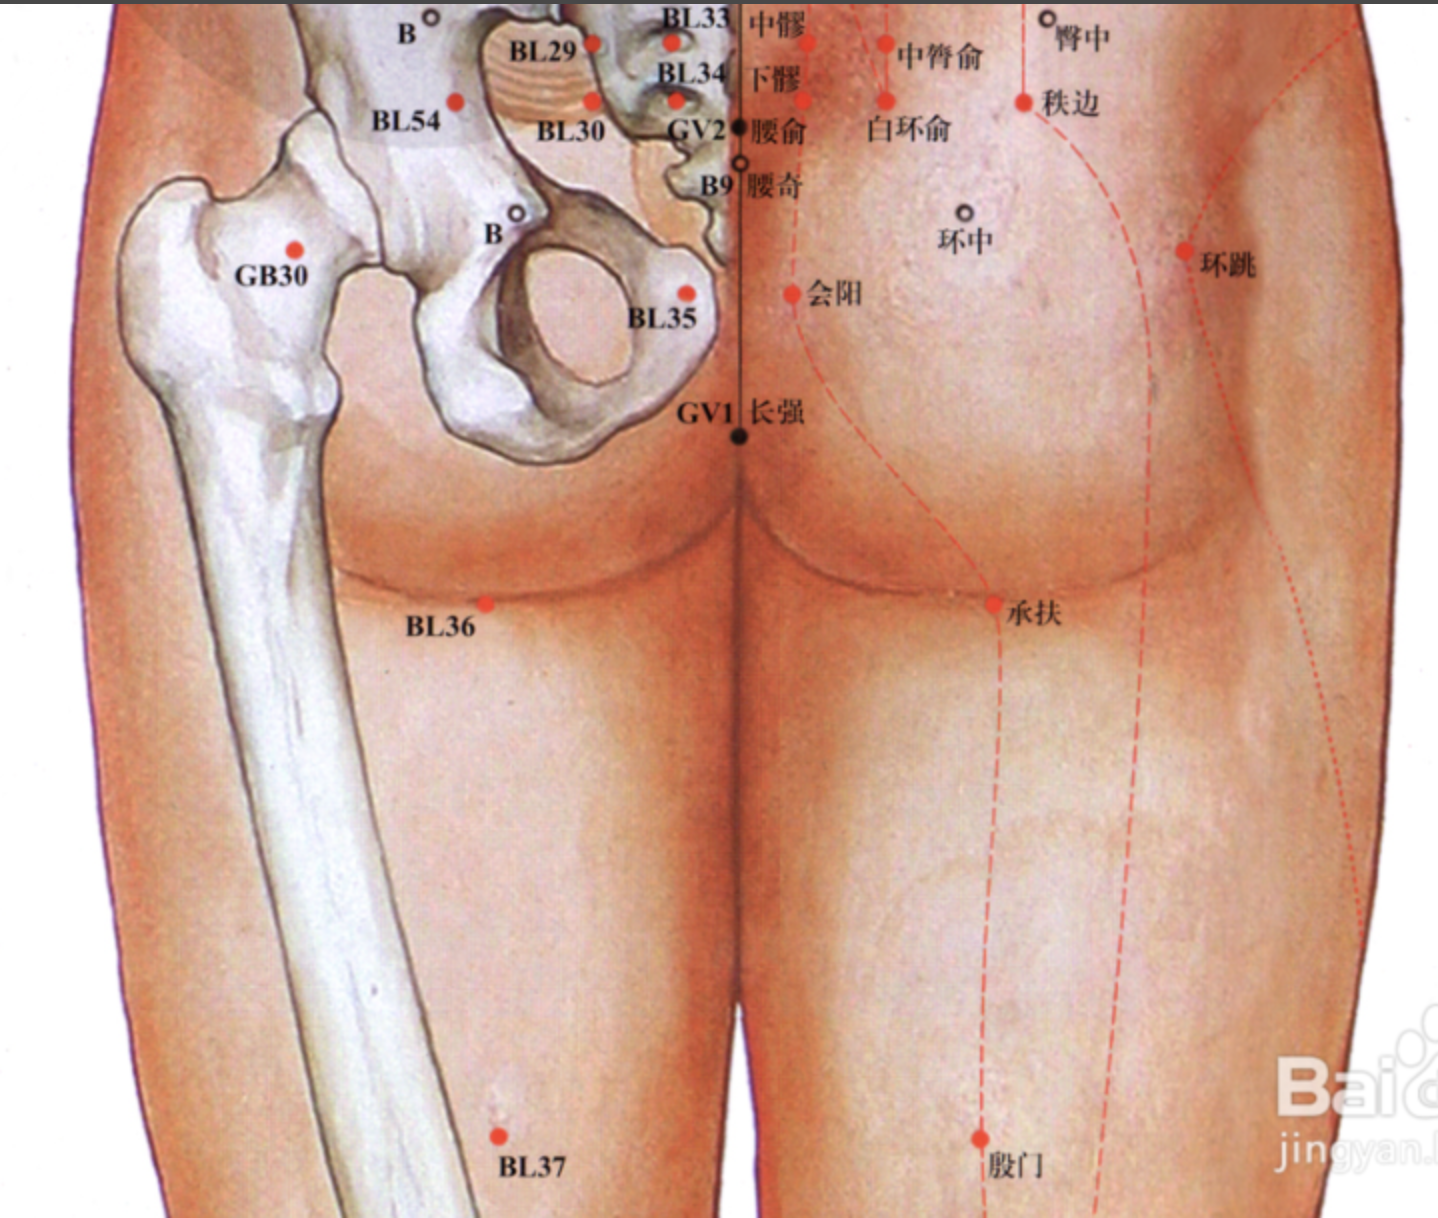

【(七)足太阳膀胱经(图 10-25-1)】

腰部支脉:向下通过臀部,进入腘(guó)窝内。

后项部支脉:通过肩胛骨内缘直下,经过臀部下行,沿大腿后外侧与腰部下来的支脉会和于腘窝中。从此向下,出于外踝后,第五趾骨粗隆,至小指外侧端(至阴),与足少阴经相接。

4、主要病候 小便不通,遗尿,癫狂,疟疾,目痛,见风流泪,鼻塞多涕,鼻衄,头痛,项、背、臀部及下肢循行部位痛麻等。

3、主治概要 主治头、项、目、背、腰、下肢部病证及神志病,背部第一侧线的背俞穴及第二侧线相平的腧穴,主治与其相关的脏腑病证和有关的组织器官病证。

委中

【定位】 在腘横纹中点,当肱二头肌肌腱与半腱肌肌腱的中间。

【主治】 腰痛,下肢痿痹,腹痛,吐泻,小便不利,遗尿,丹毒。

【配伍】 配大肠俞治腰痛。

【刺灸法】 直刺 1 ~ 1.5 寸,或用三棱针点刺腘静脉出血。

【附注】 足太阳经所入为“合”;膀胱的下合穴。

环跳

【定位】 在股外侧部,侧卧屈股,当股骨大转子最凸点与骶管裂孔连线的外 1/3 与中 1/3 交点处。

【主治】 腰胯疼痛,半身不遂,下肢痿痹,遍参风疹,挫闪腰痛,膝踝肿痛不能转侧。

【配伍】 配风市治风痹,配太白、足三里、阳陵泉、丰隆、飞扬治下肢水潴留、静脉炎,配风市、膝阳关、阳陵泉、丘墟治胆经型坐骨神经痛,配居髎、风市、中渎治股外侧皮神经炎,配髀关、伏兔、风市、犊鼻、足三里、阳陵泉、太冲、太溪治小儿麻痹、肌萎缩、中风半身不遂。

【刺灸法】 直刺 2 ~ 2.5 寸;可灸。

【附注】 足少阳、太阳二脉之会。